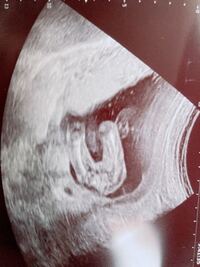

妊娠18週3日(18w3d)の赤ちゃんのエコー写真です。投稿も募集しています。 2回目の4Dエコーです! 順調みたいで安心o(^ ^)o 性別も女の子だろうねーとの事! 健康に産まれてくれればいい! と一番に思ってますが、理想としては 最初の子は女の子がいいねと 私は、体毛(まさに、腹毛)が濃くなるタイプで女の子を二人産みました。 今、妊娠7ヶ月で赤ちゃんは女の子っぽいと言われてますが、やはり体毛が濃くなってます。 ただの体質だと思いますよ。 1431 1852 17

妊娠してすぐ性別が分かるわけではありません。 はやくて妊娠5か月、遅いと8か月くらいなんてこともあるんです。 それまでワクワクしながらその時間過ごすのも楽しいですよね。 そして、いざ性別が分かった!旦那さんにどうやって伝えよう!と思ったねんれい 22歳 妊娠週 23w3d 写真はお股を真下から撮ったものです。 性別は前回女の子と言われ、今回もやはり何も付いてないので女の子とのことでした^^体重が647gになっててこの1ヶ月間で3倍にまで成長していて驚きました! ! 身長は約30cmだそうです